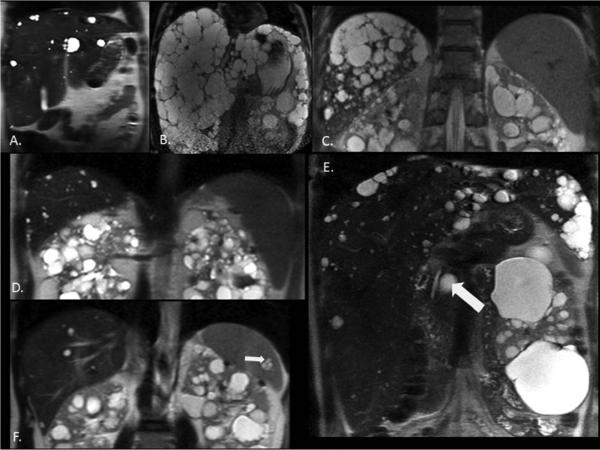

Figure 2. MR images illustrating.

(A) Hepatomegaly (TLV 2677 mL) with larger contribution of LPV (2576 mL) compared to LCV (101 mL); (B) Hepatomegaly (11834 mL) with larger contribution of LCV (9806 mL) compared to LPV (2028 mL); (C) Splenomegaly (601 mL) associated with severe PLD(3388 mL) with LCV (1044 mL); (D) Splenomegaly (542 mL) associated with moderate PLD (LV 2082 mL, LCV 110 mL) (E) Pancreatic cyst (diameter 21.8 mm) (F) Splenic cysts (diameter 12.2 mm).

As expected, htLCV correlated positively with htLV, particularly in severe PLD (Figure 1A) (females r=0.69; males r=0.48). After reaching an htLCV threshold of ~700 mL/m, htLPV does not continue to increase (Figures 1B, Figure 2A, 2B). Because most of these cases are women, the trends of htLV, htLCV, and htLPV (in Figure 1B) account for the lower LPVs in women with compared to those without liver cysts (1555±289 vs. 1735±448 mL, P=.0003, Table 2). Thus, while LPV is normal or larger compared to healthy normals in the majority of ADPKD patients, relative reductions in htLPV occur in a small subset with severe PLD (Figure 1B,).

We used the data depicted in Figure 1B to classify the extent of PLD into mild, moderate, and severe. We arbitrarily defined mild PLD as htLV <1000 mL/m, and considered htLV between 1000 - 1800 mL/m to represent moderate PLD. We defined severe PLD as htLV >1800 mL/m, (women were 81%) concordant with the plateauing of htLPV at this cutoff point, which approximately corresponds to htLCV >700 mL/m. Table 3 compares demographic, laboratory, and imaging characteristics of patients according to PLD severity. Alternatively arbitrary htLCV cutoffs can be used to define disease (Supplemental Table 5). Patients with severe PLD were older (females in their fourth decade) with lower platelet counts, albumin, eGFR, quality of life, and higher alkaline phosphatase (ALP), alanine aminotransferase (ALT), height adjusted spleen volume (htSV) (Figure 2C).